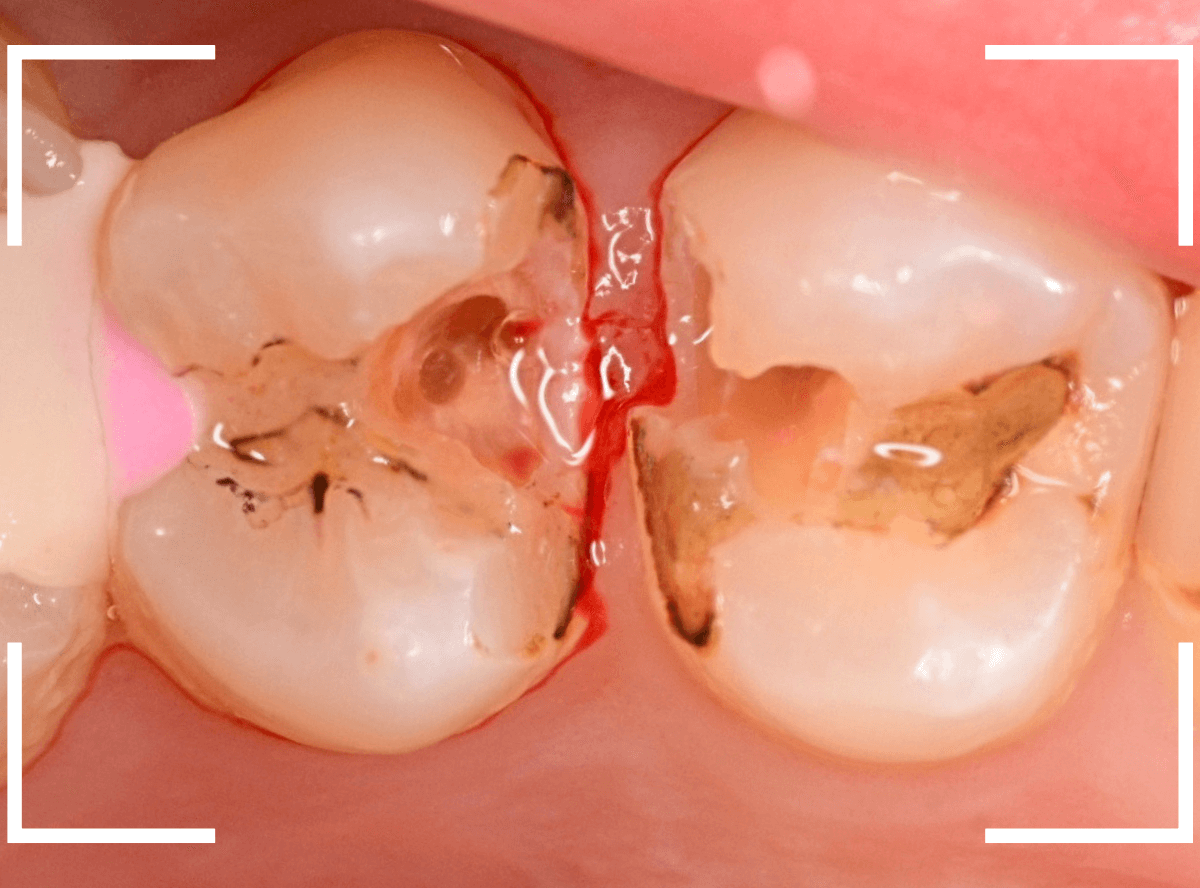

Case.8 虫歯が原因で歯がかけた虫歯

奥歯で物を噛んだ時に違和感がある、という訴えで来院された方です。

奥歯の歯と歯の間がかけていて、大きな虫歯になっているのが外から見てもわかります。

レントゲン写真で確認します。

赤い線が虫歯の部分、青い線が歯の神経です。

特に手前の歯の虫歯が神経に触れそうなほど近い虫歯になっています。

これでは、いつ大きな痛みが起こってもおかしくありません。

麻酔をかけて、治療を開始します。

金属のつめものを慎重に外したところです。

あちこちが虫歯になっていますね。

全ての虫歯を除去したところです。

両歯とも、神経スレスレのところまで虫歯になっていました。

痛みが出ないように、お薬をつめて経過観察をします。